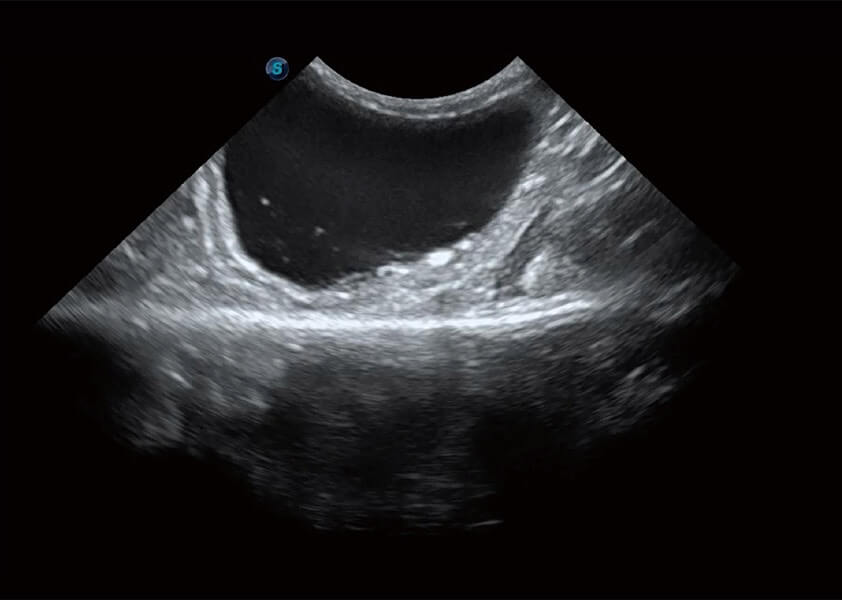

ProPet 60 作为一款高端台式动物超声设备,为动物医生的日常诊断提供了一系列贴合动物临床需求、解决临床实际问题的高级成像功能。凭借全系列高清探头,满足医生对腹部、心脏、生殖、浅表、肌骨等成像的所有需求,切实帮助您提升检查效率,提高诊断信心。

动物是人类最亲密的朋友和最值得信赖的伙伴。米兰官方网站也一直致力于探索动物专用的超声影像解决方案。 全新推出的ProPet系列,是米兰官方网站在动物超声影像智能化、专业化、精准化的一次跨越式革新。动物不能用言语来表述自己的不适,通过超声影像,ProPet系列搭建了动物医生与不同物种沟通的“桥梁”,为动物医生注入了“治愈之力”。